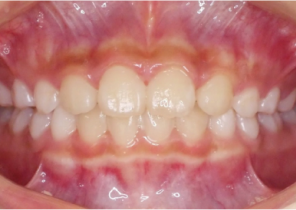

Report sul Caso 1

10 anni 0 mesi, 18 fasi di Invisalign Palatal Expander

Per gentile concessione della Dott.ssa Sandra Khong Tai

Pre espansione Invisalign Palatal Expander

Post espansione Invisalign Palatal Expander

Dopo il trattamento Invisalign First